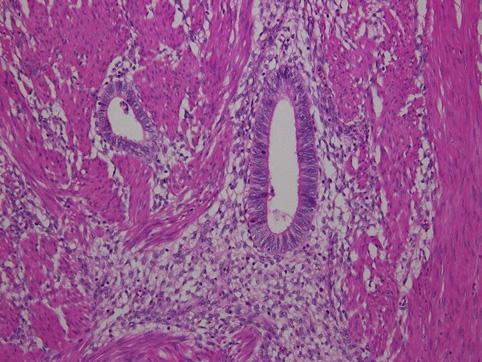

疾病(病理主体)的分类肿瘤样病变/子宫内膜症

部位(按器官分)大肠/直肠

检查方法病理切片(微观)